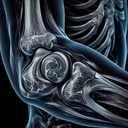

МРТ плечового суглобу

Магнітно-резонансна томографія (МРТ) плечового суглобу — це неінвазивний метод дослідження, який використовує потужні магнітні поля та радіохвилі для отримання детальних зображень структури плеча. Цей метод є дуже інформативним для діагностики різних захворювань і травм, наприклад: 1. **Оцінка м'яких тканин**: МРТ допомагає виявити розриви та пошкодження сухожиль, м'язів і зв'язок...